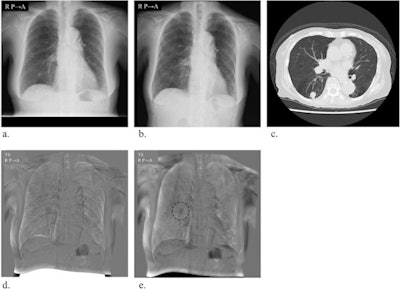

In previous studies, bone suppression has improved radiologists' detection of lung nodules on digital chest x-rays. In this reader study, the researchers examined differences in detection between conventional TS (C-TS) and TS using bone suppression (BS-TS).

Five radiologists were recruited to evaluate images processed using both the C-TS and BS-TS techniques. Images were selected from 31 patients with lung disease, including 19 with primary lung cancer, eight with lung metastases, and four with pneumonia. A majority of patients' lesions were classed as subtle, very subtle, or extremely subtle on prior CT scans.

The performance -- as assessed by figure-of-merit values -- of all radiologists increased significantly using the bone-suppression method, from 0.619 (conventional) to 0.696 (p = 0.032). The average sensitivity for detecting pulmonary lesions improved from 67.9% to 75.4%, and the average number of false positives per case decreased from 0.336 to 0.252 using bone suppression temporal subtraction.